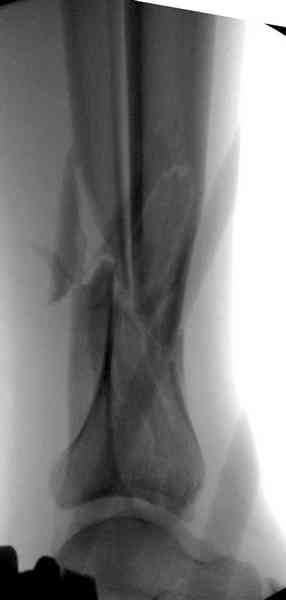

При высокоскоростных переломах редко можно встретить изолированную травму пилона, и в моей практике изолированные травмы большая редкость, поэтому, как дополнение к обсуждаемой теме, решил представить свежий, двухдневной давности случай.

Предыдущей сменой до 4:00 утра по поводу открытого перелома бедра, тибиал плато, пилон и надколенника сделана операция.

Пострадавшему 21 г., травма скоростная, после I&D с расширением раны, на бедре сделана операция ретроградным интрамедуллярным штифтом, остеосинтез с частичной резекцией надколенника и ушивание собственной связки.

На голень наружный фиксатор, рану на бедре ушили (рана была изнутри кнаружи всего 2 см). По протоколу травматических больных, до операции обследован ангиографически, (у больного дистально не смогли определить пульсацию) сосудистый хирург подтвердил проходимость на всем протяжении магистрального сосуда нижней конечности по снимкам ангиограмм.